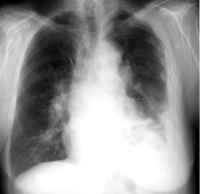

The

most common place for mesothelioma to develop is in the mesothelial membrane,

also called the pleural lining, surrounding the lungs. About two-thirds of

all mesothelioma cases develop in the pleural mesothelium or lung lining.

Pleural mesothelioma is also known as cancer of the lung lining.